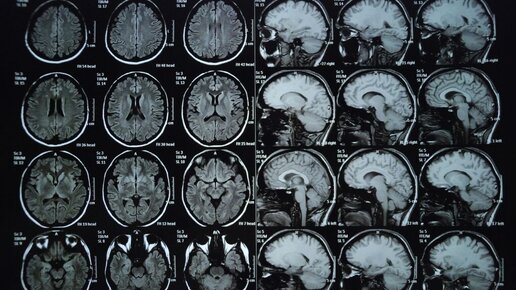

Ученые Центра языка и мозга НИУ ВШЭ подтвердили участие мозолистого тела в распределении языковой обработки между полушариями мозга. Для этого они разработали уникальное речевое задание и применили современные методы нейровизуализации. Статья опубликована в Plos One. Работа выполнена при поддержке мегагранта правительства России в рамках нацпроекта «Наука и университеты». Функциональная асимметрия высших когнитивных функций — уникальное свойство человеческого мозга. Примером асимметрии является язык человека, обработка которого у большинства людей происходит в левом полушарии...